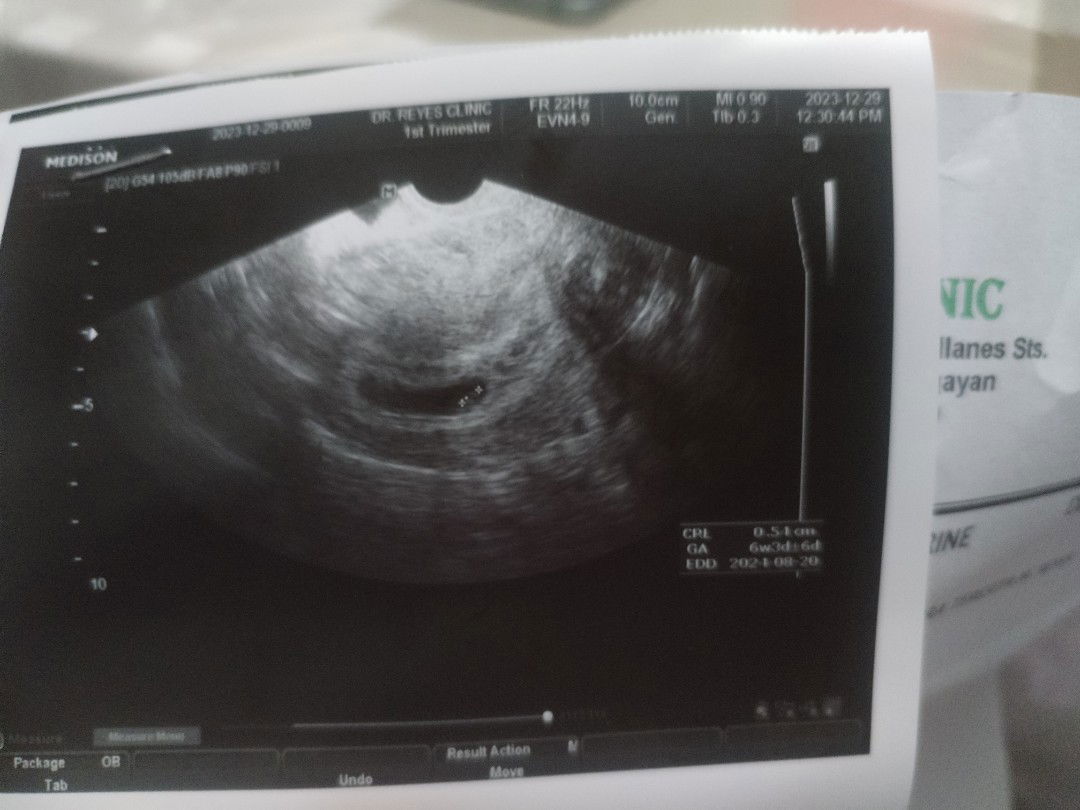

Preggers